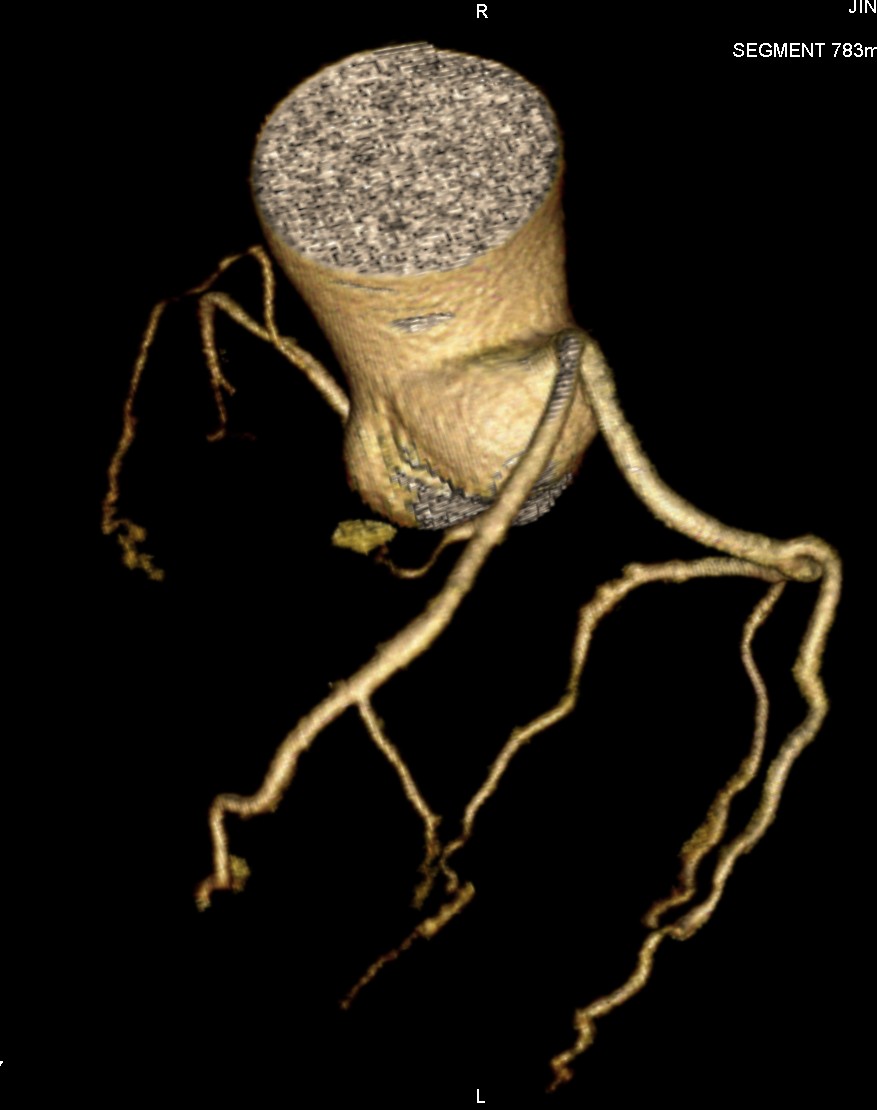

标题: CT24400:患者54岁,心前区不适进行心脏冠脉造影检查。 [打印本页]

标题: CT24400:患者54岁,心前区不适进行心脏冠脉造影检查。

患者54岁,心前区不适进行心脏冠脉造影检查。高手看看有问题没有?

图像很漂亮,好像未见异常